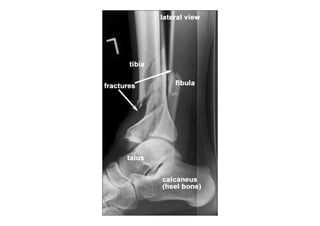

RADIOLOGIA DO

TRAUMA DO ESQUELETO

Referência: http://www.accessexcellence.org/RC/VL/